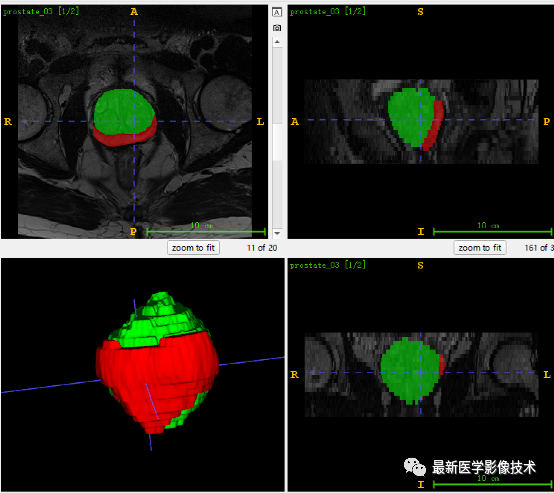

6、测试集分割结果